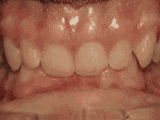

前牙反合,俗稱“地包天”,也就是咬牙時,下牙蓋住上牙,正常情況應(yīng)該是上牙蓋住下牙,經(jīng)過矯正后的牙齒可以變成這樣的~